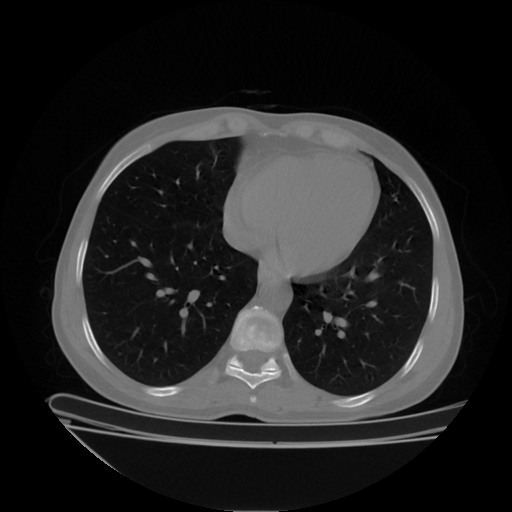

Original VENOUS CT scan

Full window (WL 1023.5, WW 4095 β†’ Low βˆ’1024, High +3071)

Actual HU range: [-1024.0, 1080.0]

Lung window (WL -600, WW 1500 β†’ Low βˆ’1350, High +150)

Actual HU range: [-1350.0, 150.0]